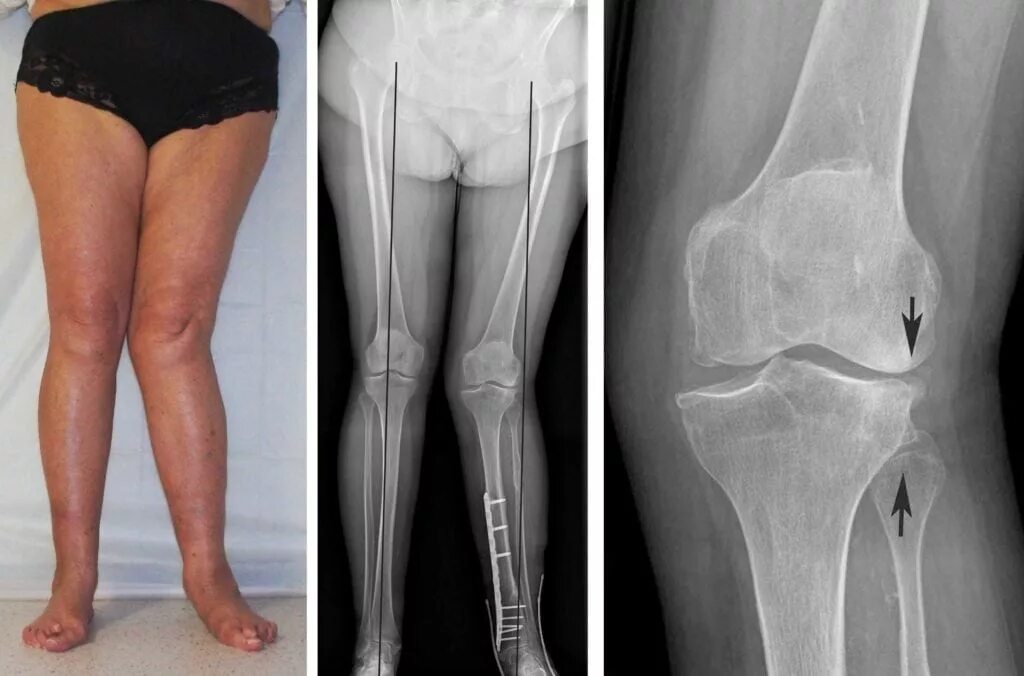

Вальгусная деформация коленных суставов у ребенка